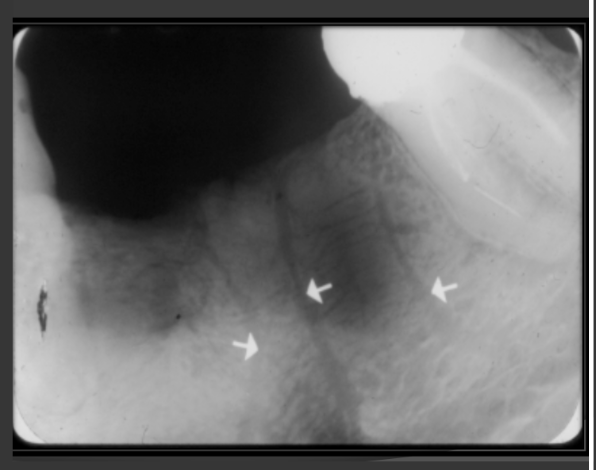

How does the genial tubercles/mental spines present in a radiograph?

Presents as a ring shaped radio opacity (white donut). Sits below the centrals on the mandible. It is the white portion. The radiolucent dot is a different structure

How does the lingual foramen present in a radiograph?

Presents as a tiny radiolucent dot below the mandibular centrals. Looks like a white donut because it is overlapping with the genial tubercle.